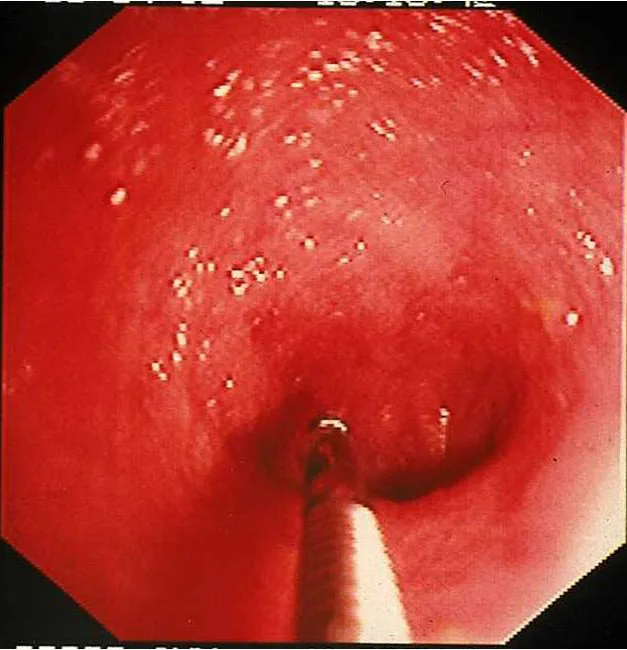

The best biopsies are obtained by directing the instrument at a 90° angle (perpendicular) to the mucosal surface at flexure locations (A). (Note the numerous white spots along the mucosa, which are areas of light reflection, not lymphangiectasia.) Flexure sites facilitate targeted, deep mucosal tissue purchases while reducing the tendency of the forceps cups to slide along the superficial mucosa. Tissue biopsies procured at nonflexure sites will require directing the endoscope tip (and biopsy forceps) obliquely toward the mucosa.

If the patient is large, use of a “long-distance” biopsy technique may be warranted. The biopsy forceps is passed as far as possible down the lumen until resistance is met. Usually the forceps cups are beyond the operator’s view distally (B). Once resistance is encountered, the forceps are retracted slightly (to open up the jaws) then readvanced firmly against the mucosa where a tissue specimen is obtained (C).